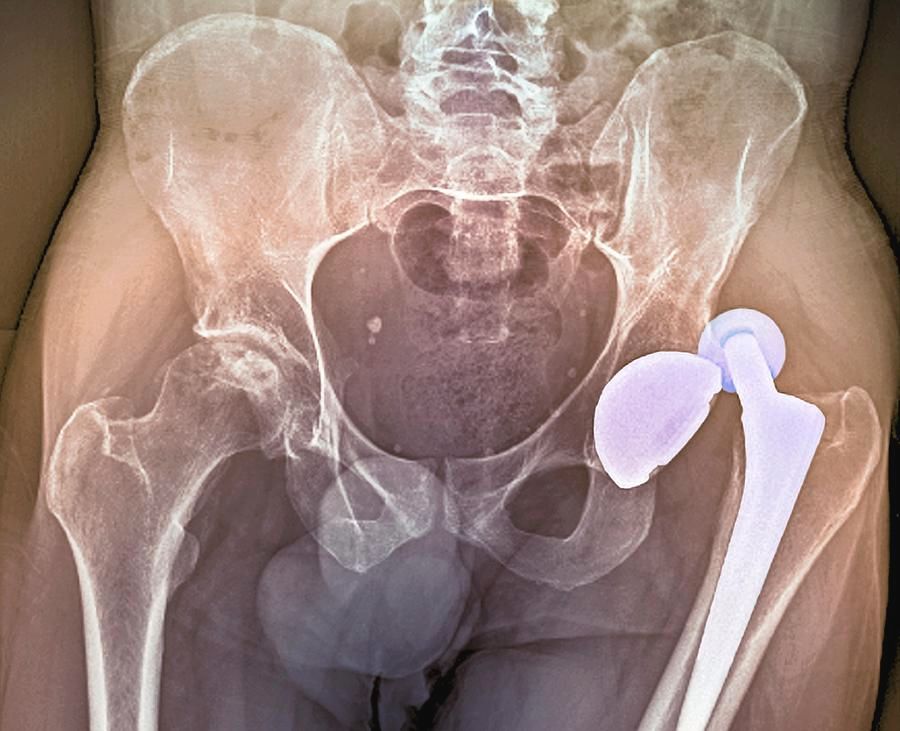

Patient-16 is another hip replacement by Dr. Michael Bradford at Nevada Orthopedic & Spine Center resulting in long-term pain and suffering for the patient. The patient's hip has dislocated 6 times since surgery. Dr. Bradford will not return phone calls or provide medical care to the patient.

My wife broke her hip, and Dr. Bradford (with Nevada Orthopedic & Spine Center) performed her surgery on May 24, 2025, at Sunrise Hospital.

Since the surgery, her hip has dislocated 6 separate times. This last time, she was told that Dr. Bradford finally called back after hours of trying to reach him.